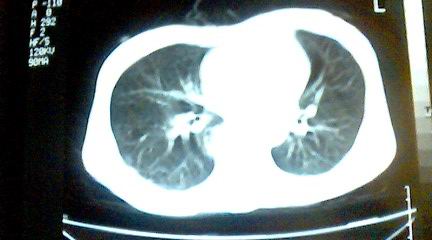

标题: CT25218:请教!胸部CT,胸8椎体骨质破坏,伴周围软组织肿。 [打印本页]

标题: CT25218:请教!胸部CT,胸8椎体骨质破坏,伴周围软组织肿。

患者,女41岁,肢体乏力。

双肺及胸椎结核。

两肺上叶继发性肺结核;胸椎结核并椎旁寒性脓肿形成。